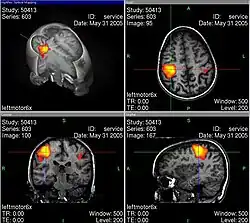

La física nuclear es conocida mayoritariamente por el aprovechamiento de la energía nuclear en centrales nucleares y en el desarrollo de armas nucleares, tanto de fisión nuclear como de fusión nuclear, pero este campo ha dado lugar a aplicaciones en diversos campos, incluyendo medicina nuclear e imágenes por resonancia magnética, ingeniería de implantación de iones en materiales y datación por radiocarbono en geología y arqueología.Física de partículas o de altas energías